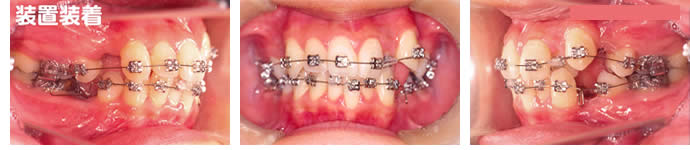

■装置装着直後

上下左右各1本ずつの抜歯をおこないました。上下の顎にブラケットを装着し、でこぼこやねじれをとってゆきます。同時にヘッドギアも夜のみ開始しました。